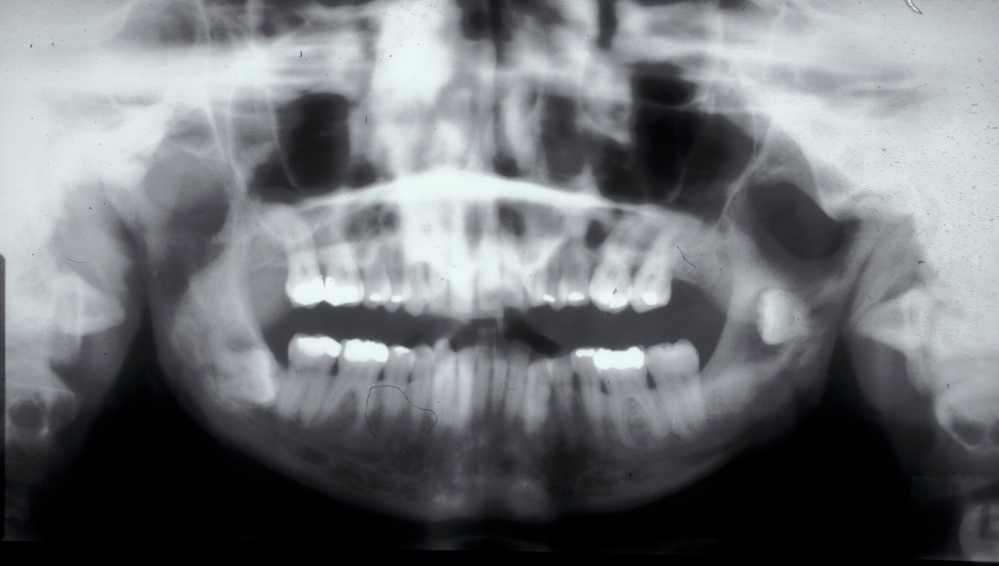

Assessment of the tooth is both clinical and radiographic. If somebody presents in pain, it is important to establish that this is coming from the third molar and not elsewhere. Pain is often vague, poorly localised and may be referred from another tooth, or as part of facial arthromyalgia (condition affecting the jaw joint). A dental panoramic radiograph is ideal as it helps to assess all the teeth at once. The health of the adjacent molars may influence the decision whether to remove the third molar or not. Large crowns or old restorations are all at risk of dislodgement during surgery. It is also worth considering whether alternative treatment options are available. For instance, pericoronitis due to an over-erupted upper third molar may be dealt with by extracting that tooth only, with or without operculectomy. In the presence of other teeth of poor prognosis, will it be better in the long term to save the third molar which may be used as a denture or bridge abutment in the future?

These points help to determine whether the tooth can be simply elevated or will need a surgical approach. A series of radiographs depicted in Figure 4 to Figure 8 illustrate these points further.